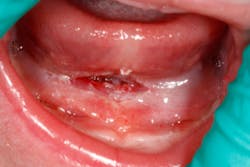

The time spent performing the laser surgery for this frenectomy was less than one minute (figure 5)!

Figure 5: Immediately post-op